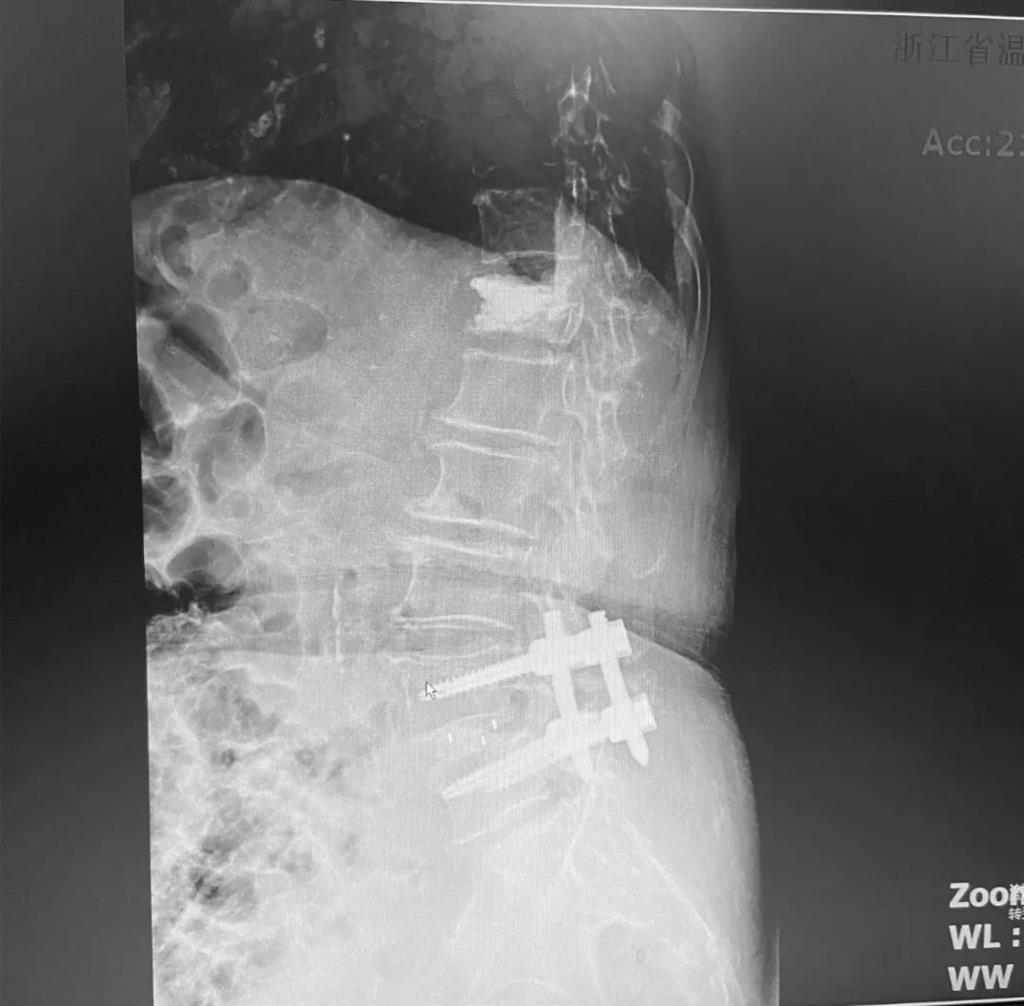

據(jù)了解,脊柱內(nèi)鏡下腰椎融合術(shù)只需要打幾個(gè)“鑰匙孔”即可完成。聽(tīng)起來(lái)是不是很簡(jiǎn)單?在脊柱內(nèi)鏡下,劉丹主任先后為患者進(jìn)行了椎管減壓、椎間盤(pán)摘除,再實(shí)施椎弓根螺釘放置、椎體植骨融合內(nèi)固定,一系列步驟有條不紊。

看似簡(jiǎn)單的幾個(gè)步驟,但實(shí)際上很復(fù)雜,需要主刀醫(yī)生有豐富的手術(shù)經(jīng)驗(yàn)和細(xì)致耐心的操作。

術(shù)中只需切開(kāi)4個(gè)如“鑰匙孔”般大小的孔道